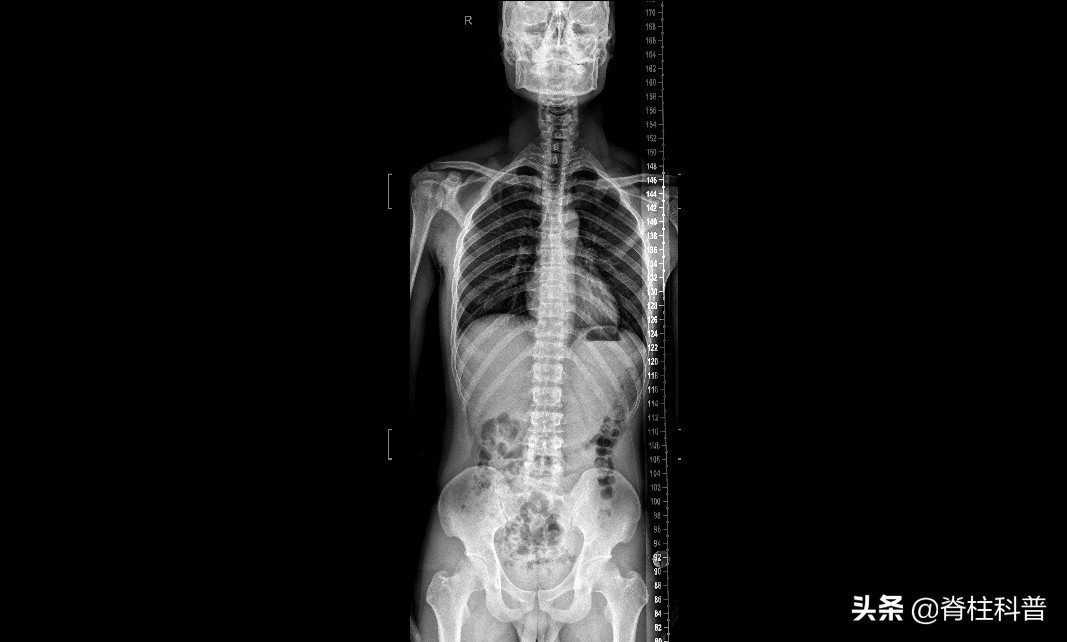

相比于CT和MRI,X线检查似乎没有优势,可以直接被取代。这样想的你们,就大错特错了。首先,相比于CT和MRI,X线检查有着明显的价格优势。其次,相对于CT来说,X线检查辐射量较小。最重要的是,在腰椎间盘突出的早期诊断中,腰椎侧位、立位片(即x光片子)有着重大作用。在早期诊断中,通过X线片子,能够观察患者的腰椎是否有生理性弯曲、腰椎间隙是否有变化、椎体周边是否形成骨刺。不要忘记了,临床上单纯腰痛的患者,仍然是大多数。对于这些患者来说,X线检查是性价比最高的检查。

X光片子

虽然X线不能用于确诊腰椎间盘突出,但它的地位依然不可替代!

X线平片对于诊断腰椎间盘突出确诊率较低,主要原因是腰椎间盘突出具备平片征象者不多,大多数病例只表现为生理曲度的改变等,以致多数病例漏诊。但X线平片对显示腰椎生理弯曲及椎间隙改变情况优于CT检查。而此表现正是X线平片诊断椎间盘突出较可靠的征象。另外对椎弓根崩裂、椎体滑脱、椎体及小关节增生、压缩性骨折、肿瘤、结核、化脓性炎症等诊断与鉴别诊断均具有一定价值。因此不要认为X线平片对腰椎间盘突出诊断率低就拒绝做此检查。还是上面说的那句话,对一项疾病的诊断,除了有正向思维外,还有反向思维。尽可能的收集详细的临床证据,才能极大程度上降低误诊、漏诊率!